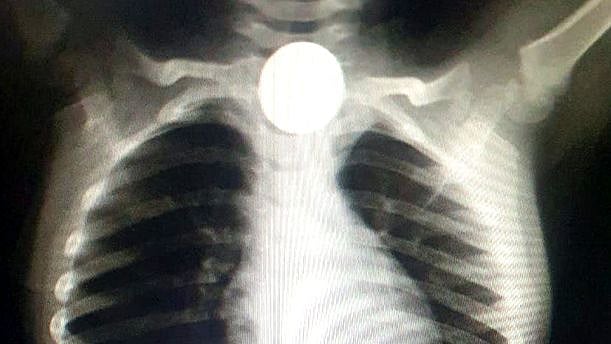

இதையடுத்து சிறுவனை திருவண்ணாமலை அரசு மருத்துவமனைக்கு அழைத்துச் சென்றனர். அங்குச் சிறுவனுக்கு ஸ்கேன் செய்து பார்த்தபோது உணவுக்குழாய் தொண்டைப்பகுதியில் நாணயம் சிக்கிக் கொண்டிருப்பதை மருத்துவர்கள் உறுதி செய்தனர்.

பின்னர் தொண்டை துறையின் தலைவர் மருத்துவர் இளம் செழியன் மேற்பார்வையில் சிறுவனுக்கு மருத்துவர்கள் சிகிச்சை அளித்தனர். பிறகு “LARYNGOSCOPY“ முறையில் அறுவை சிகிச்சையின்றி, சிறுவனின் தொண்டையில் சிக்கிய ஒரு ரூபாய் நாணயத்தை மருத்துவர்கள் வெற்றிகரமாக அகற்றினர். பின்னர் சிறுவனின் உடல் நிலை இயல்பு நிலைக்கு திரும்பியதும், வீட்டிற்கு அனுப்பிவைத்தனர்.